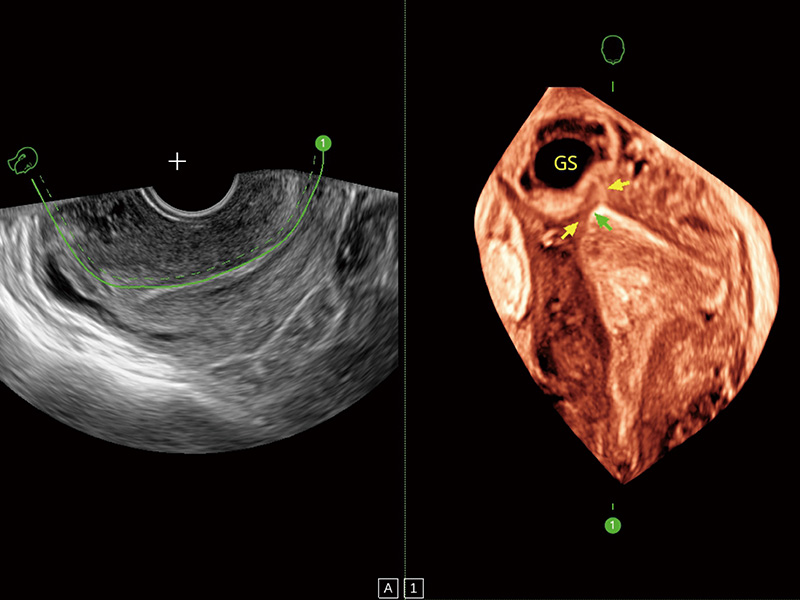

中央型宫腔粘连

单角子宫